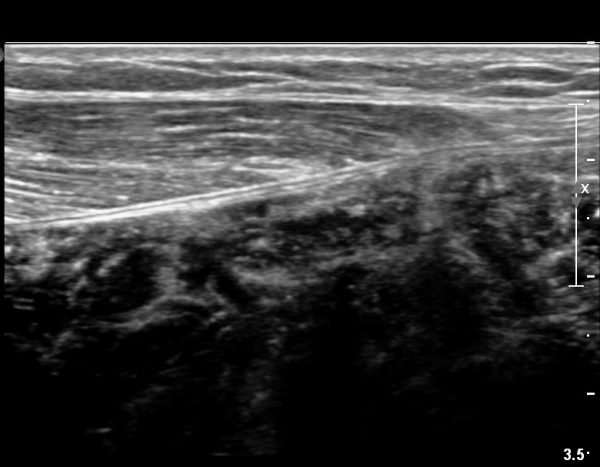

[¹ß¸ñ] simultaneosus tear of GCM and achiles tendon

abrupt leg pain developed during foot volleyball

he walk with severe limping with no weight bearing on rt. leg. on examination, there is local tendernes at GCM and achiles tendon, severe pain with ankle dorsiflexion.

ÃÊÀ½ÆÄ °Ë»ç

rec) short leg splint with crutch gait. he refused splint, then visit other hospital and took operation.